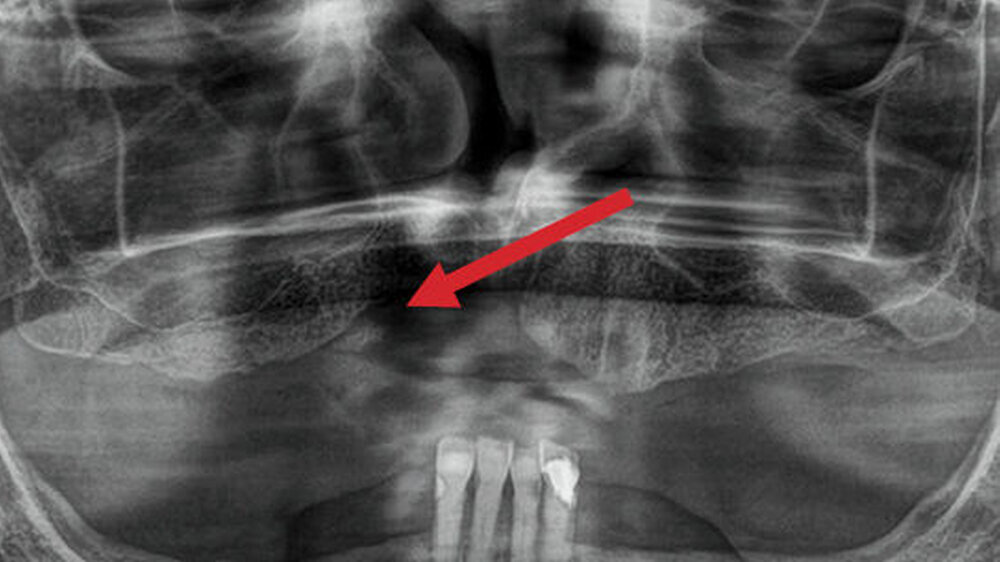

In diesem Patientenfall geht es um eine 65-jährige Patientin, die infolge einer Bisphosphonat-Applikation fünf Jahre zuvor bereits eine Dekortikation und plastische Defektdeckung im anterioren Oberkiefer erfahren hatte. Der resultierende keilförmige Defekt ist auf der Panoramaschichtaufnahme deutlich zu erkennen (Abbildung 1).

Im DVT sind in allen Raumebenen deutliche Knochendefekte zu erkennen, die zur Unterbrechung des Alveolarfortsatzes in der OK-Frontzahnregion führen. Zusätzlich grenzt sich ein breiter Canalis incisivus ab (Abbildungen 2 bis 4). Ein Rückschluss auf Pathologien im bezeichneten Bereich lässt sich aus den vorliegenden radiologischen Unterlagen nicht ziehen.